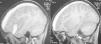

Niño de 7 años sin antecedentes personales de interés que consulta por cefalea holocraneal de un mes de evolución, con vómitos matutinos. No refieren ningún traumatismo craneal reciente. Se realiza fondo de ojo en el que se aprecia edema de papila bilateral. En la tomografía computerizada (TC) craneal realizada a continuación se observa una lesión hiperdensa en cisura de Silvio (fig. 1-A). En la TC con contraste, se aprecia un hematoma subdural subagudo-crónico hemisférico izquierdo, con moderado efecto masa que desplaza línea media (fig. 1-B). En la RM craneal se aprecia una colección extra-axial en lóbulo temporal izquierdo y cisura de Silvio con contenido hemático comunicado con el hematoma subdural (figs. 2 y 3), compatible con quiste aracnoideo complicado. Se realiza craneotomía izquierda urgente con evacuación completa del hematoma subdural, siendo alta a los cinco días sin secuelas neurológicas. La angio-TC realizada 15 días más tarde descarta aneurismas cerebrales u otras causas de sangrado, persistiendo una imagen compatible con quiste aracnoideo silviano izquierdo. Actualmente el niño está asintomático, con seguimiento ambulatorio.